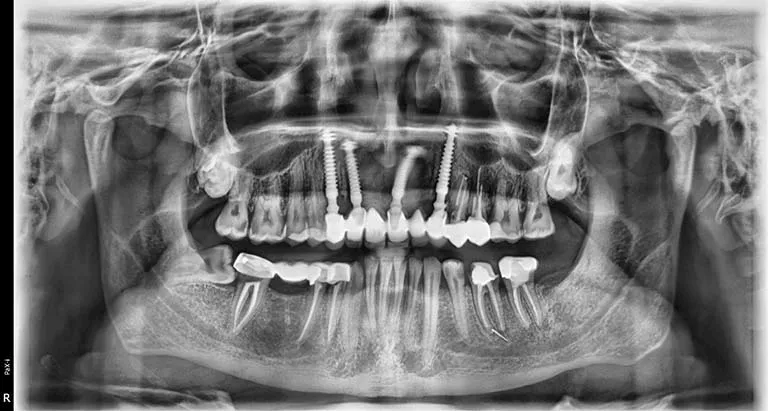

وأشار إسلام إلى أن معاناته بدأت بعد العملية مباشرة، إذ لم تلتئم اللثة رغم مرور ستة أشهر، وبدأ يشعر بإعياء ومشكلات دفعته للتوجه إلى طبيب آخر، والذي طلب منه إجراء أشعة مقطعية وأشعة بانوراما. وقال إنه فوجئ بتشخيص الطبيب بوجود تآكل شديد بعظام الفك العلوي في مواضع الزرع، ووجود خُراجين صديديين، بالإضافة إلى استقرار أحد مسامير الزرعات داخل الجيب الأنفي، وعدم ثبات الزرعات في مكانها.

وأوضح أن عدة أطباء أكدوا له أن هذه المضاعفات نتجت عن العملية، وأن الطبيب الذي أجرى الزراعة لم يطلب أي فحوصات أو إشعات قبلية، مشيرًا إلى أن بعض الأطباء رفضوا كتابة تقارير طبية بالحالة “حتى لا يضعوا أنفسهم في موقف محرج مع الزملاء”.

وأكد إسلام أن الطبيب ع.ع أنكر النتائج التي أظهرتها الأشعة، زاعمًا أن مشكلته تقتصر على ضرورة إزالة مسمار واحد فقط، بينما تنصّل الطبيب الآخر أ.ع صاحب المركز الذي أُجريت به العملية، من المسؤولية وطالبه بالرجوع للطبيب الأول.